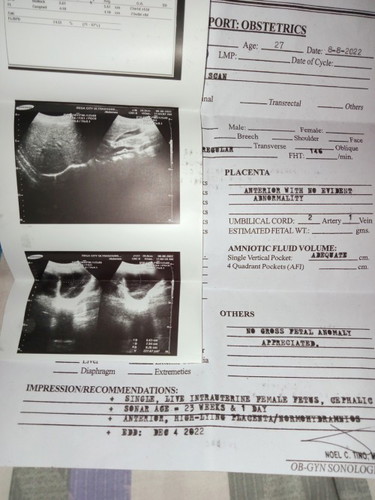

tanong lang 23weeks and 1day nakalagay sa ultrasound, Firsttime mom lang po ilang months n po ba eto

Hello 👋🏻 6 and half months. Ako kasi 22 weeks na 6 and half months sabi ng OB.

Momsh 6mos na po kayong buntis. 😊

kita na po sya maam 5months, sabi sakin ng midwife magssixmonth palang ngayong 13 pina explain ko po yung ultrasound First ko po ksi kaya medyo wala pong alam🤭,